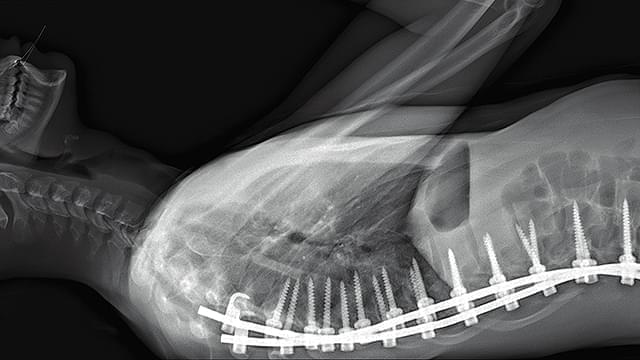

パリ北部近郊の5つの病院のオペ室を舞台に、普段は決して見ることのできない手術時の医師視点のカメラや内視鏡カメラなどの映像を使用しながら、脳や大腸、眼球、男性器などさまざまな外科手術や帝王切開の模様を映しだす。さらに、死と隣りあわせの職場で働く医療従事者たちの心境や、死体安置所での「おくりびと」たちの仕事ぶりをとらえ、医療とは何か、そして肉体と魂とは何かという疑問を探る。